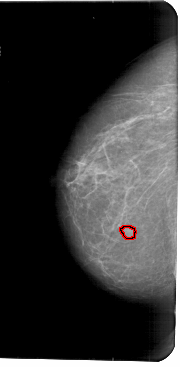

A_1776_1.LEFT_CC

LEFT_CC LINES 5491 PIXELS_PER_LINE 2686 BITS_PER_PIXEL 12 RESOLUTION 43.5 OVERLAY

FILE: A_1776_1.LEFT_MLO.OVERLAY

TOTAL_ABNORMALITIES 1

ABNORMALITY 1

LESION_TYPE MASS SHAPE IRREGULAR MARGINS ILL_DEFINED

ASSESSMENT 4

SUBTLETY 3

PATHOLOGY BENIGN

TOTAL_OUTLINES 1

BOUNDARY